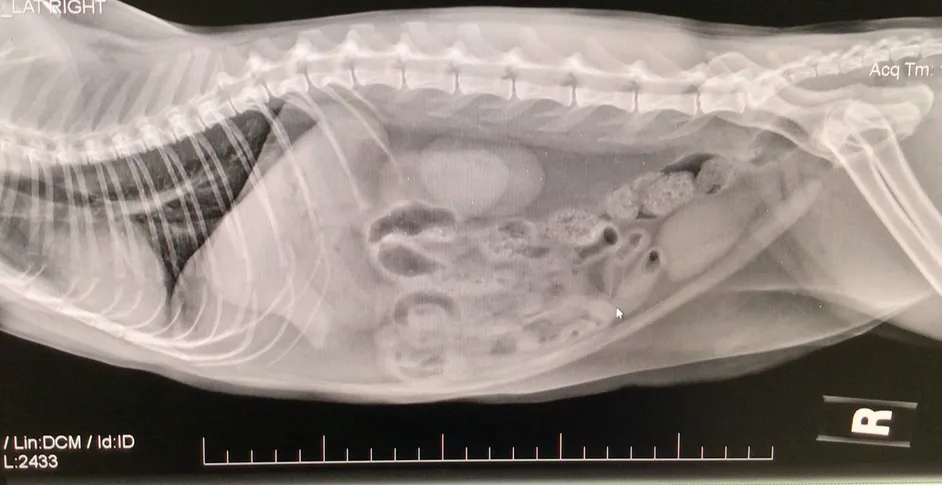

rads

• Digital imaging and radiography

• Abdominal ultrasound